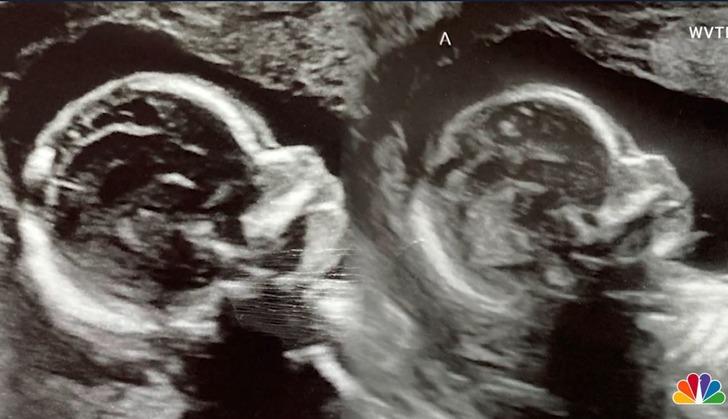

MYNET DIŞ HABER-Kelsey Hatcher isimli kadın çok az rastlanan bir hastalığa sahip. Uterus Didelphy hastalığı olan Alabamalı kadın gündeme bomba gibi düştü. İki rahmi bulunan genç kadın ikiz bebek bekliyor beklemesine ancak bebekler farklı rahimlerden doğacak.

Alabama Üniversitesi Hastanesi'nde kadın hastalıkları ve doğum uzmanı olan Dr. Richard Davis, 1000 kadından sadece 3'ünün iki rahimle doğduğunu ve her ikisinde de hamile kalma şansının en az milyonda 1 olduğunu söyledi. Davis, Hatcher'a hamileliği boyunca danışmanlık yapıyor ve ultrasonlarının çoğuna yardımcı oluyor.

Sağlıklı bir şekilde büyüyen bebekler ayrı yumurtalardan geliyor ve özdeş olmayacaklar, bu nedenle Davis "çift yumurta ikizleri" teriminin onları tanımlamak için daha doğru bir yol olabileceğini öne sürdü.